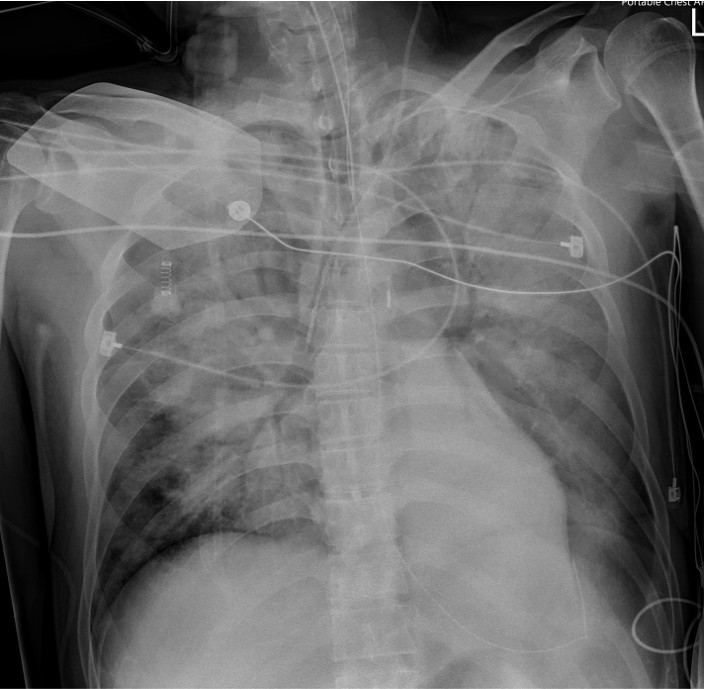

A 50-year-old man with hypertension and ulcerative colitis on vedolizumab developed dyspnea and chest tightness while visiting Taiwan. On February 28, he collapsed after bathing with pulseless electrical activity arrest. Cardiopulmonary resuscitation for 48 minutes achieved return of spontaneous circulation. Electrocardiogram showed ST elevation in aVR with diffuse ST depression. Lactate was 11.5 mmol/L. ECMO and IABP were initiated for cardiogenic shock.

Relevant Test Results Prior to Catheterization

Electrocardiogram showed ST elevation in aVR with diffuse ST depression (V4–V6), suggesting left main or triple-vessel ischemia. Echocardiography revealed a severely reduced LVEF of 10–20%. Laboratory tests showed creatinine 1.37 mg/dL, AST/ALT 161/119 U/L, and lactate 11.5 mmol/L. Chest CT demonstrated bilateral dependent consolidation without aortic dissection, consistent with a STEMI equivalent and cardiogenic shock.